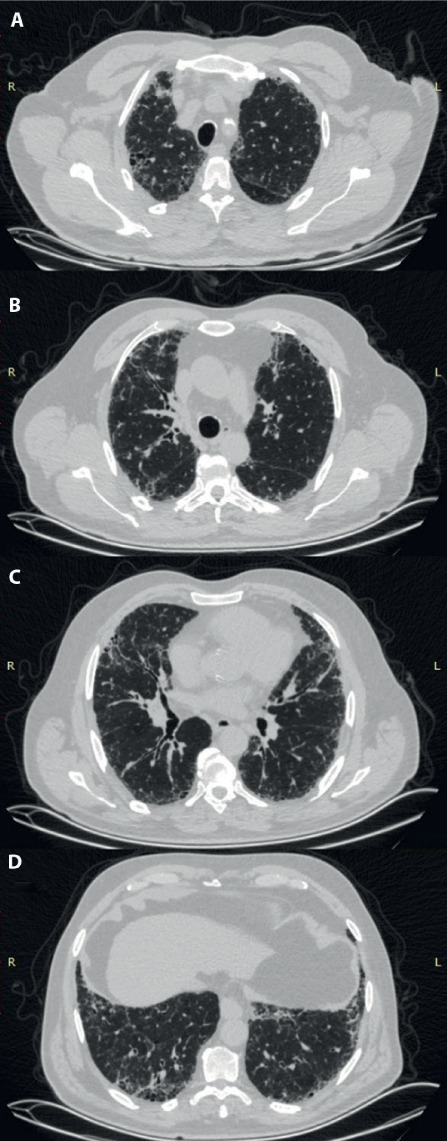

超敏性肺炎(HP)是一种复杂的免疫介导的间质性肺病(ILD),由遗传易感个体吸入环境或职业抗原引发。经常发现新的暴露源和抗原。然而,在近一半的HP病例中,病原体仍未确定。早期诊断为非纤维化HP并停止接触可能会防止疾病发展为纤维化形式和相关并发症。在这里,我们介绍了两例与榛子农业中榛子壳、叶和壳中霉菌暴露相关的HP病例。

Hypersensitivity pneumonitis (HP) is a complex immune-mediated interstitial lung disease (ILD) triggered by inhalation exposure to environmental or occupational antigens in genetically susceptible individuals. Novel exposure sources and antigens are frequently identified. However, the causative agent remains unidentified in nearly half of HP cases. Early diagnosis for nonfibrotic-HP and quitting the exposure may prevent the disease progression to fibrotic forms and related complications. Here, we present two cases of HP associated with mold exposure in hazelnut husks, leaves, and shells in hazelnut agriculture.